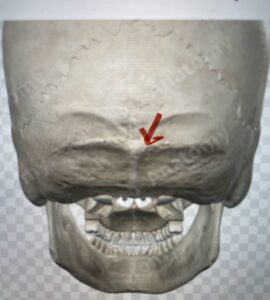

Although some patients do not require a decompression and just require an occipital cervical fusion, most require some sort of decompression of the neural elements. After a decompression an instrumented fusion is performed. A useful anatomic structure for anchoring the top portion of the construct to the skull is the midline keel of the subocciput. This structure extends from the external occipital protuberance, which corresponds to the confluence of the sagittal and transverse sinuses, to just above the foramen magnum:

(Fig. 1). This bone is quite thick, about 15 mm (Figs. 2a and b). Most modern plate systems utilize three midline keel screws with the option to place within a 2 cm lateral fixation point. This plate is connected to sometimes tricky-to-bend rods and connected to screw fixation points in the cervical spine (Fig. 3). Bone graft material extends from skull to cervical spine.

Fig. 2b: Axial CT scan of the brain demonstrating the thickness of the midline keel (red arrow) compared to the more lateral subocciput (red dot) making the keel ideal place for screw fixation